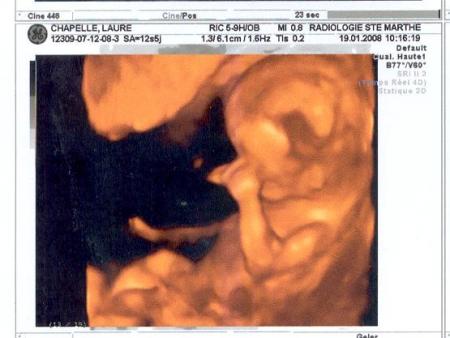

en 3 D.

27/11/2008 20:08 par lauremanulucas

toujours à l'écho du 2ème trimestre. j'ai séléctionné pour vous mon plus beau profil! 147 battements par minute. tout va bien!